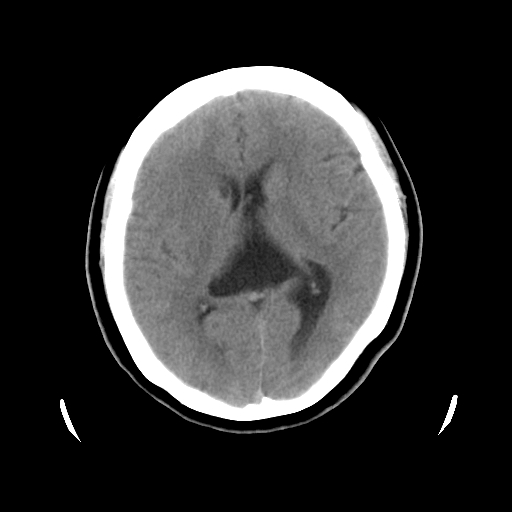

以下是引用cgf在2010-1-3 17:53:00的发言:[br]此病例多考虑:透明隔发育异常 透明隔囊肿可能性大;右侧基底节区(尾状核头)小片状低密度影考虑陈旧性腔梗[br][br]透明隔发育异常:包括透明隔间腔(第五脑室)、韦氏腔(第六脑室)、透明隔囊肿、透明隔缺如;前两者属于正常变异,后两者属于发育畸形;[br]透明隔间腔向下扩张形成韦氏腔;[br]有时透明隔间腔与透明隔囊肿很难鉴别;透明隔间腔间距一般不超过0.5cm,间距大于0.5cm时应考虑透明隔囊肿;[br]透明隔缺如为两侧脑室间隔缺如、融合成单脑室畸形,可伴有智力发育异常;[br][br]

以下是引用liaoqiang在2010-1-3 16:04:00的发言:[br]考虑侧脑室脉络丛囊肿?不除外变异的威氏腔。

以下是引用江广1996在2010-1-3 20:17:00的发言:[br]考虑变异的威氏腔。不除外侧脑室脉络丛囊肿.[br]透明隔囊肿大多数偏前,在侧脑室前角之间。